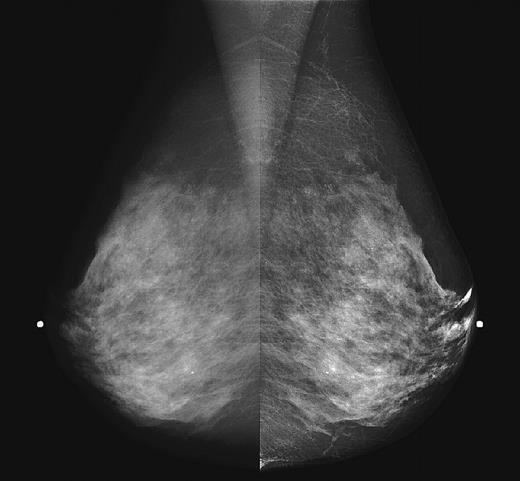

Shown above are two versions of the same left medial oblique mammogram obtained with a scanned-slot digital mammography system. On the left, the digital image has been displayed to approximate the normal contrast level of a modern film mammogram. On the right, the digital image has been processed to equalize the image for changes in breast thickness at the periphery. This provides good contrast throughout the image.

Image courtesy of Martin Yaffe, Ph.D.